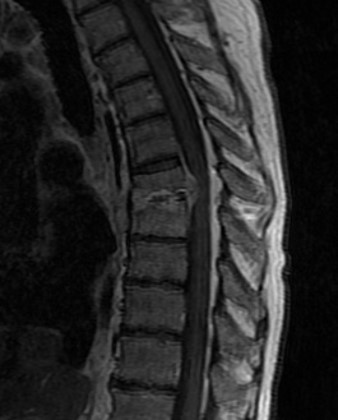

It's time for BIDMC Musculoskeletal Imaging & Intervention's interesting case of the week! ⬇️ ⬇️ ⬇️ Case # 122: History withheld. Diagnosis? Reply by Friday, March 31! #MSKRad #MedTwitter #RadRes #RadFellows

Case # 122:

History withheld.

Diagnosis?

Reply by Friday, March 31!

#MSKRad #MedTwitter #RadRes #RadFellows